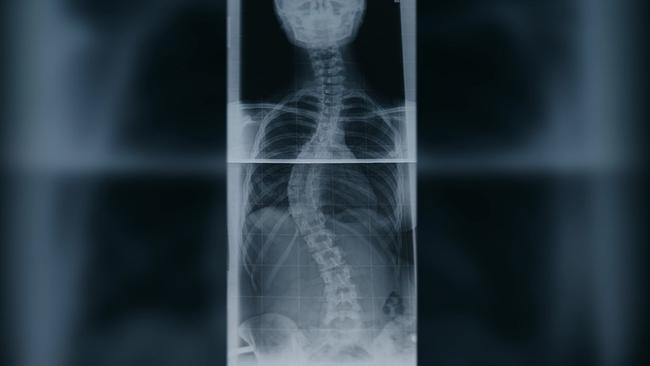

Leben mit Skoliose - Herausforderung für Körper und Seele

Der Schularzt hat bei der Salzburgerin Andrea Haderer im Alter von 12 Jahren Skoliose diagnostiziert. Darunter versteht man eine dreidimensionale Deformierung der Wirbelsäule, die besonders bei Kindern und Jugendlichen während der Wachstumsphase auftreten kann.

Sie führt zu einer mehr oder weniger deutlich sichtbaren Fehlhaltung. Je früher aber eine Wirbelsäulenfehlstellung erkannt wird, desto erfolgversprechender und schonender lässt sie sich behandeln. Ob eine Behandlung notwendig ist, hängt zum einen vom Grad der Krümmung und zum anderen davon ab, wie schnell die Krümmung voranschreitet. Leichte Fälle werden oft durch Physiotherapie und spezielle Übungen behandelt. Bei stärkeren Krümmungen kann ein Korsett helfen, das Fortschreiten zu verhindern. In schweren Fällen ist eine Operation (z. B. Versteifung der Wirbelsäule) notwendig. Andrea Haderer hat sich, nach einem sehr langen Leidensweg, mit viel Disziplin ihre Beweglichkeit und damit Lebensqualität zurückerobert.